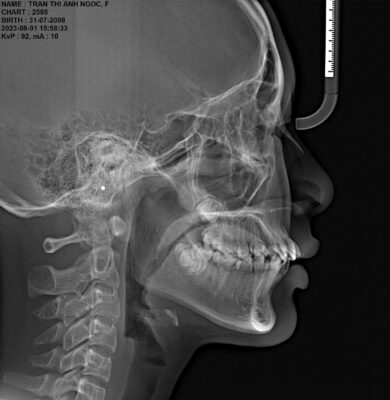

- Phim sọ nghiêng Cephalometric: Phim Cefalometric được bác sĩ sử dụng để phân tích các góc độ về răng, xương, các chỉ số mô mềm. Dựa trên các thông số này mà bác sĩ có thể xác định nguyên nhân hô, móm là do xương hay do răng, từ đó đưa ra được phương pháp điều trị hợp lý.